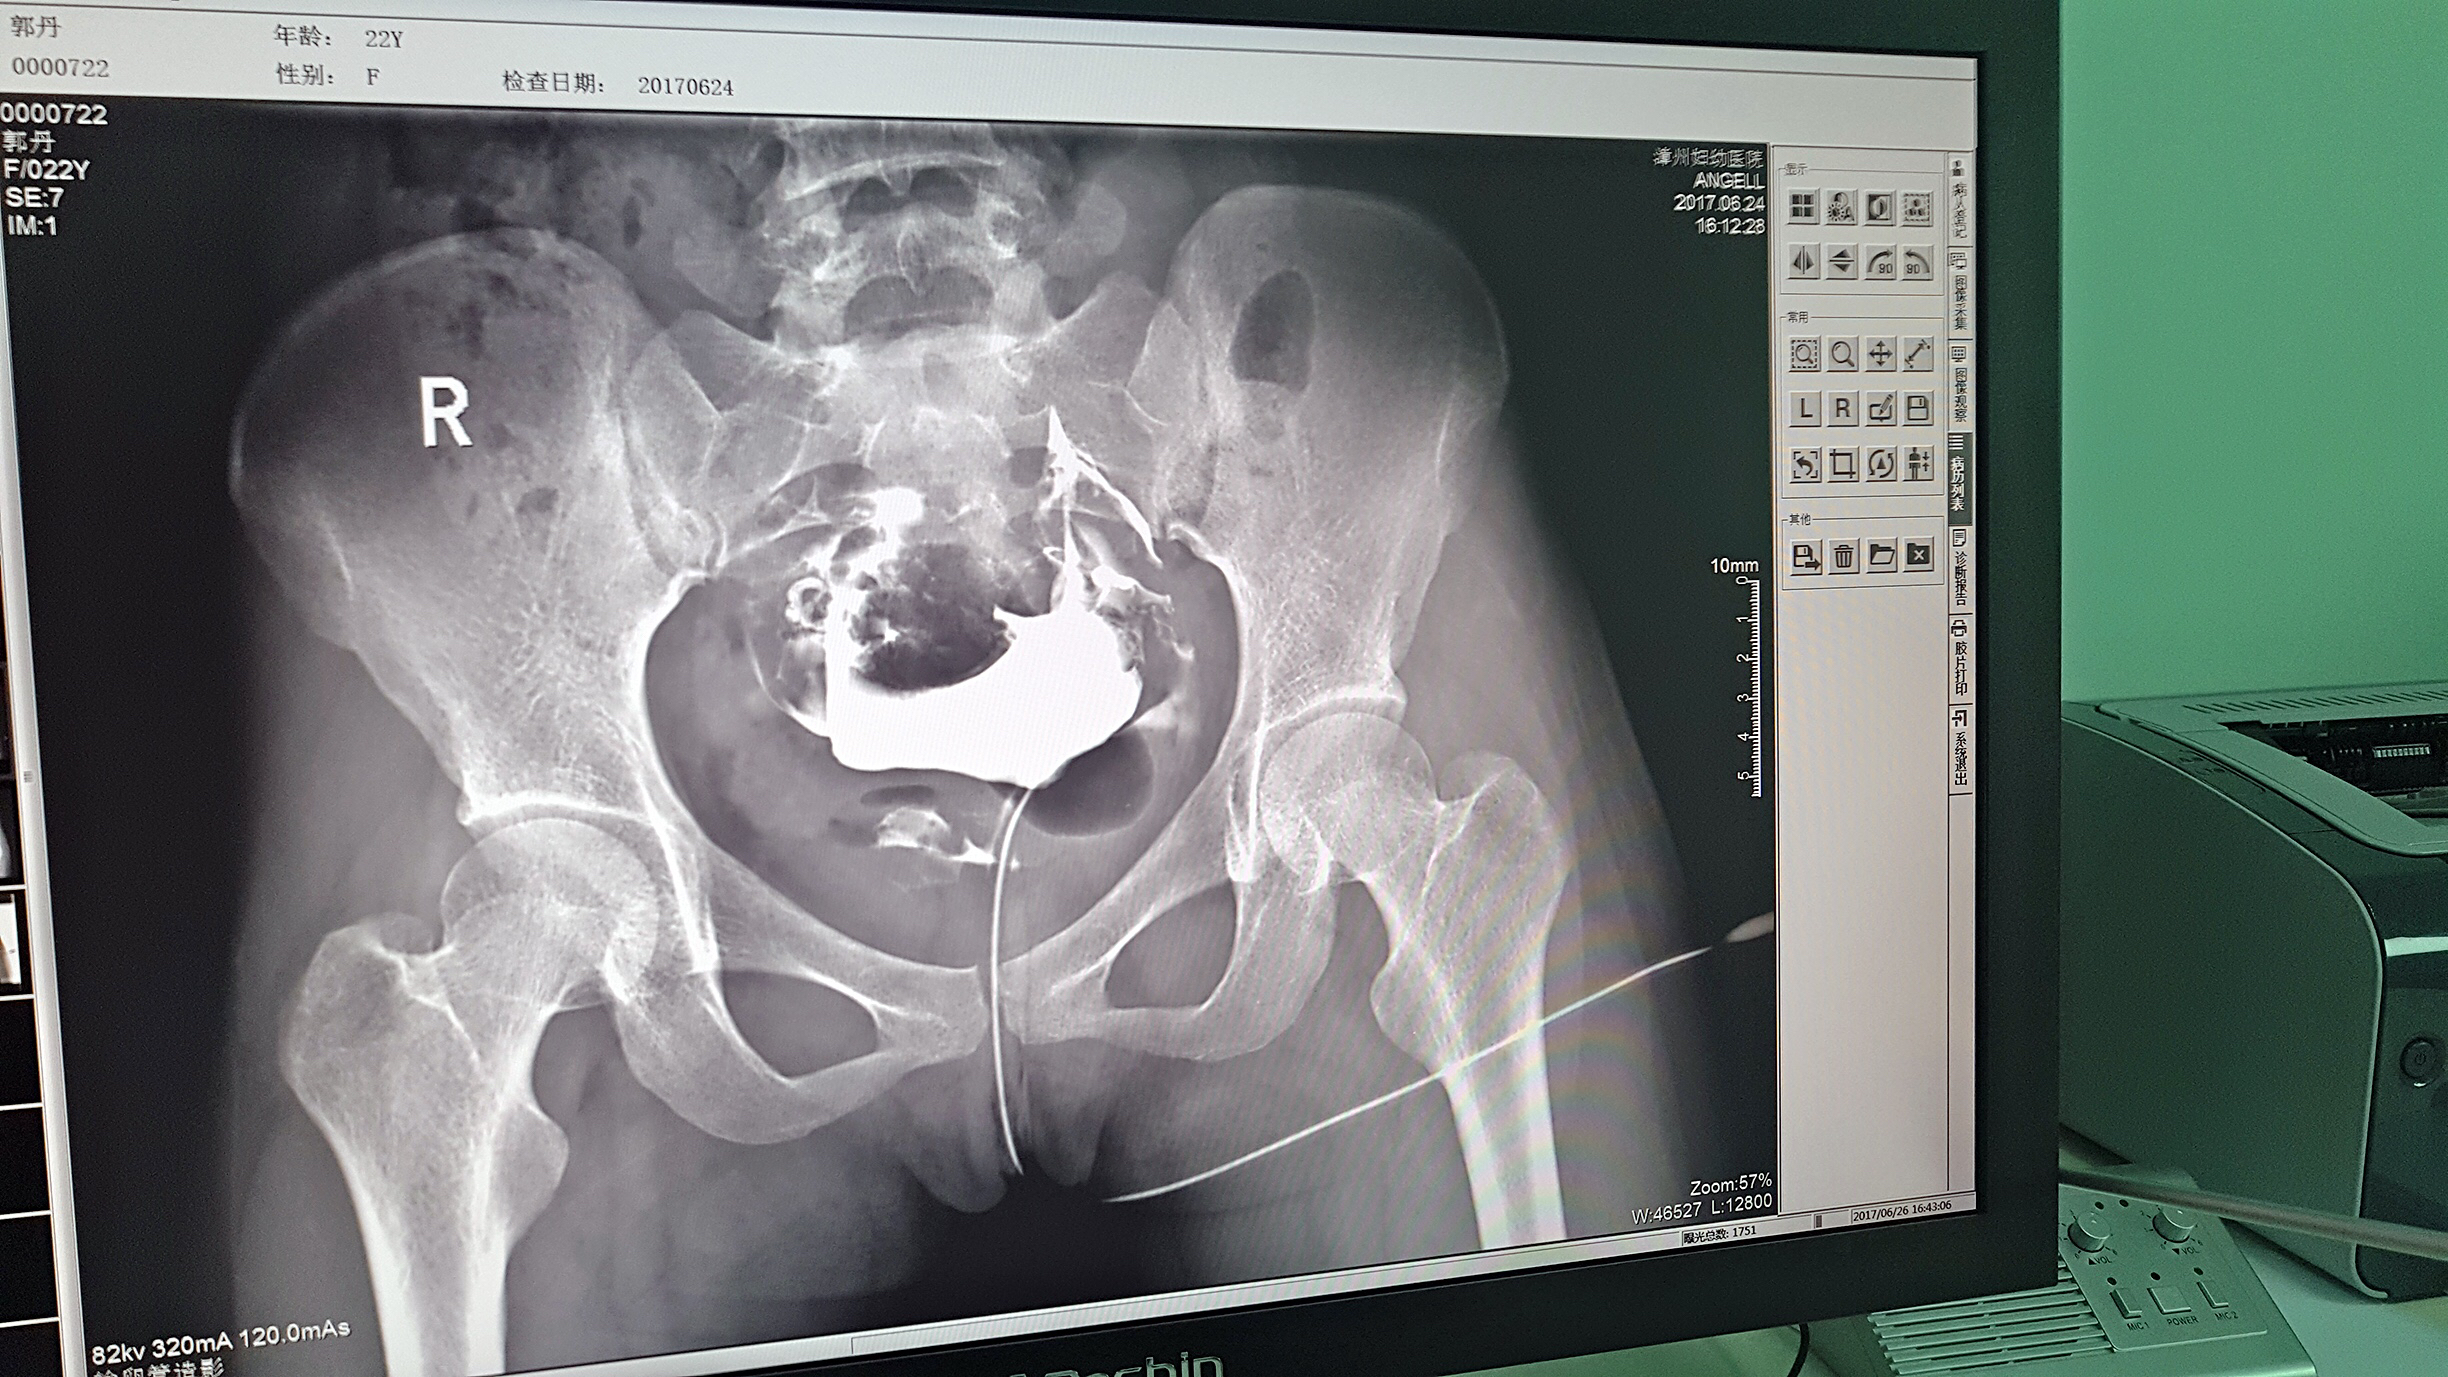

但是这家医院一直面临一个问题,妇科中输卵管检查无法完成。因为其使用的是静态DR,无法做输卵管造影检查,患者不得不前往其他医院继续检查,使得医院留不住患者,造成一笔损失。久而久之,患者可能为了图方便,直接去了其他医院治疗,这对医院经营的影响是巨大的。

2016年,漳州妇幼医院几经对比、筛选,最终选择了太阳成集团tyc122cc入口科技的动态DR产品。它选择太阳成集团tyc122cc入口科技动态DR产品的原因很简单,动态DR不仅具备普通DR的功能,还能做输卵管造影,成像质量高以及设备性价比高。

目前设备除了用于常规拍片之外,主要用于输卵管造影检查,平均每个月有超过20个患者在漳州妇幼医院做输卵管造影检查。在此之前,漳州市只有市医院、175解放军区医院等大三甲医院才能做输卵管造影检查,这不仅让三甲医院人满为患,而且下级医院却因为不能做某项检查而造成资源浪费。因为有了设备,漳州妇幼医院可以满足患者的一些特殊检查需求,已经有很多患者慕名而来。

漳州妇幼医院放射科的陈主任日常跟这台设备打交道是最多的,他最有发言权。在太阳成集团tyc122cc入口科技的回访中,陈主任说:这台设备具备先进的诊断功能,操作方便,能够拍摄出清晰的影片,进而对患者病情能够实现精准诊断。同时在医院对患者诊断能力方面有较大提升,留住了大量患者,为患者提供了更好的医疗服务。